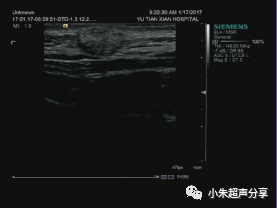

病例1  女 ,5岁,右侧颈部毛母质瘤,

周边可见少量血流信号